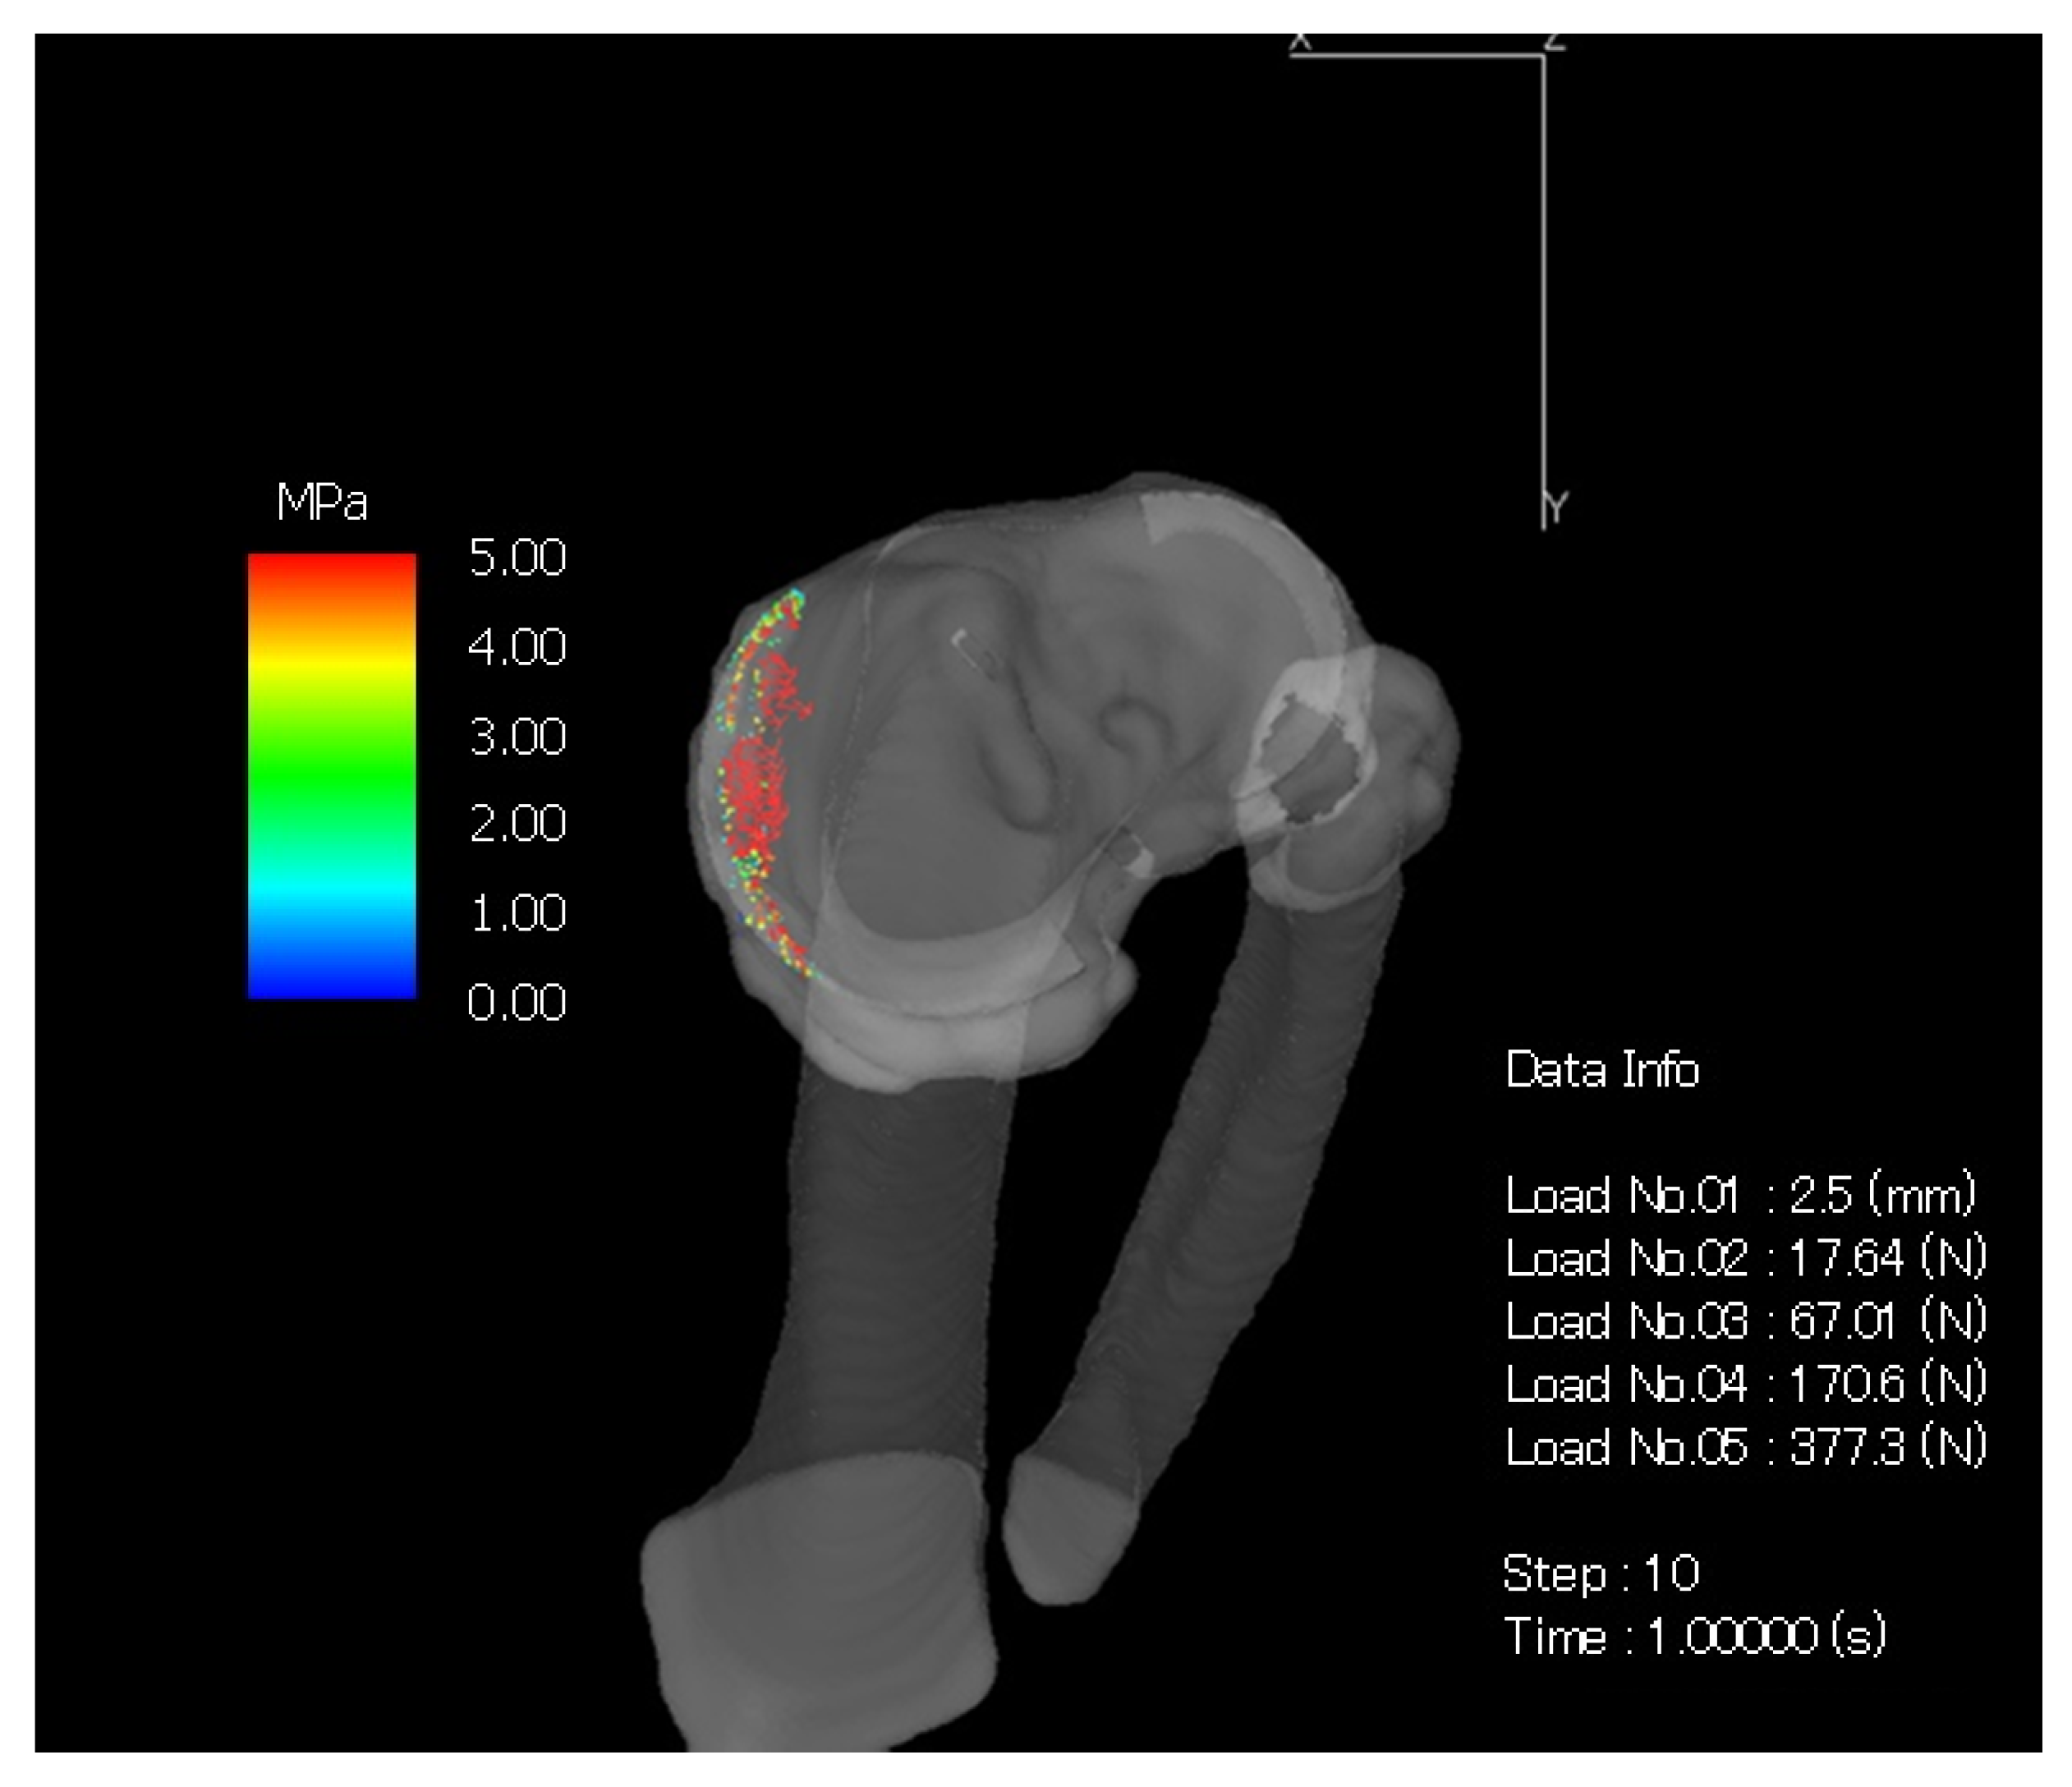

2.4. Computed Tomography-Based Finite Element Method (CT-FEM)

3. Results